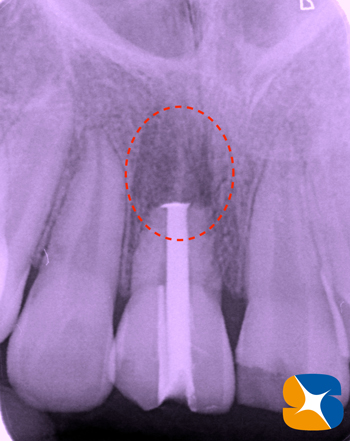

続けてCT画像でチェックも行いました。

すると、再植した根の先に、大きな膿の袋(骨がとけて腫瘍が発生)が見つかりました。

これは、今年の12月(再生治療から8ヶ月後)の状態です。膿も無くなり、骨の再生も行われ、とても良好であることが確認出来ました。